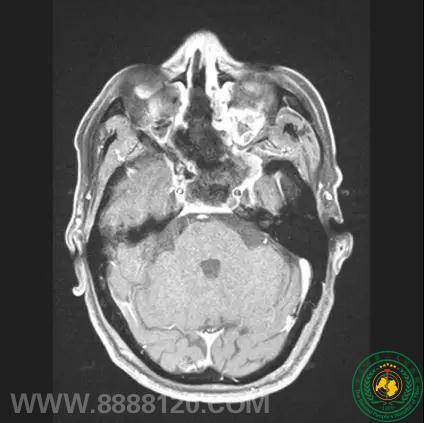

近日我院神外一科收治了一名68岁老年患者,因头痛,右眼视力障碍入院,入院后完善检查,提示为蝶窦区域巨大占位病变,约7cmX6cmX5cm大小,肿瘤压迫视神经,周围骨质破坏严重,与双侧颈内动脉及斜坡脑干紧密相连。

术前影像提示肿瘤巨大,不规则,侵袭性生长